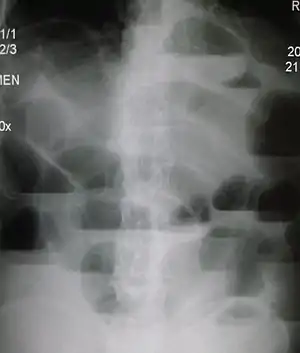

Upright abdominal X-ray demonstrating a small bowel obstruction. Note multiple air fluid levels.